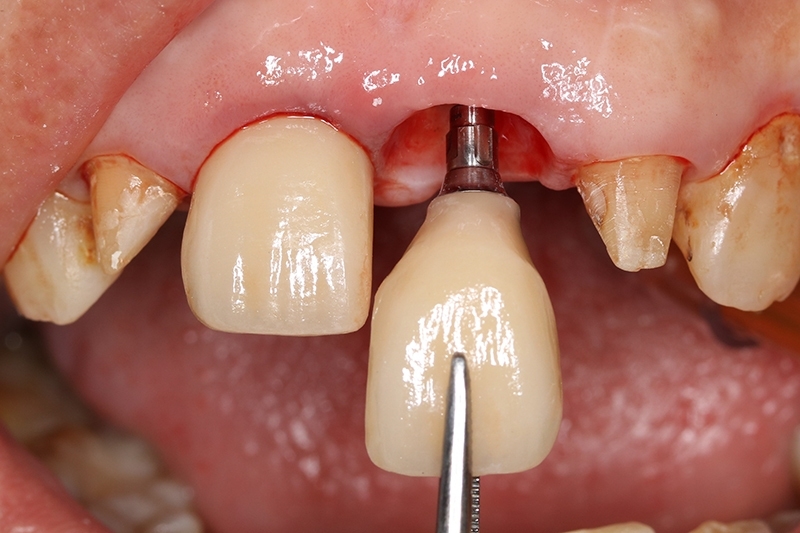

等待2個月進行植牙臨時假牙試戴

客製化金屬支台齒

植牙臨時假牙試戴2週恢復狀況